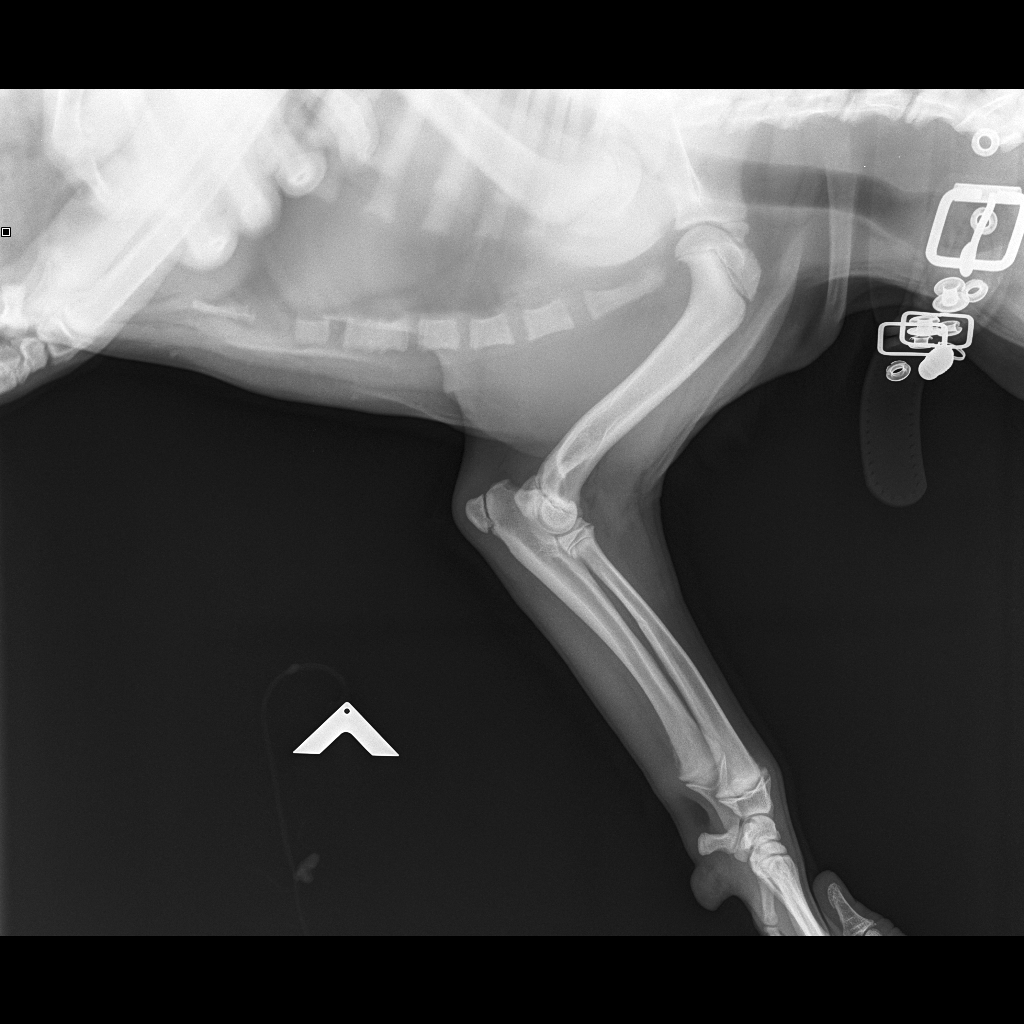

Рентген Задней Лапы Кошки: Нормы и Диагностика